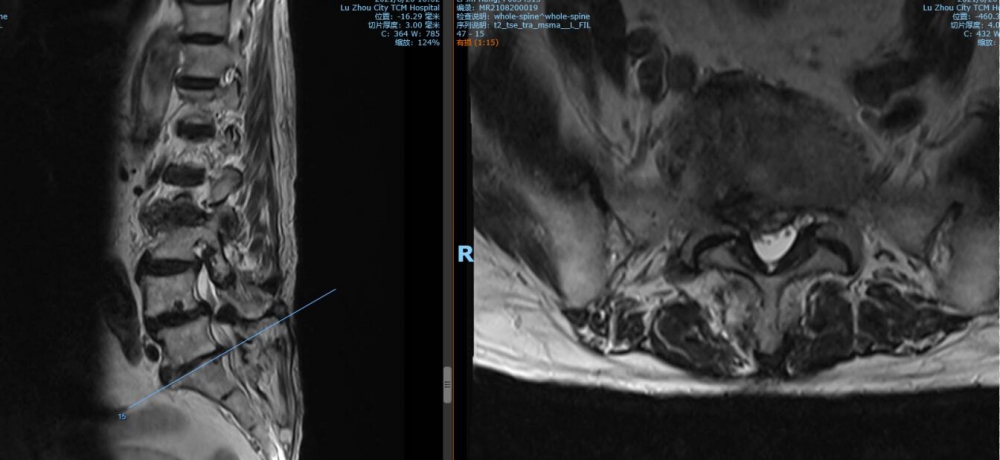

腰4 5椎間盤MRI

腰5 骶1椎間盤MRI